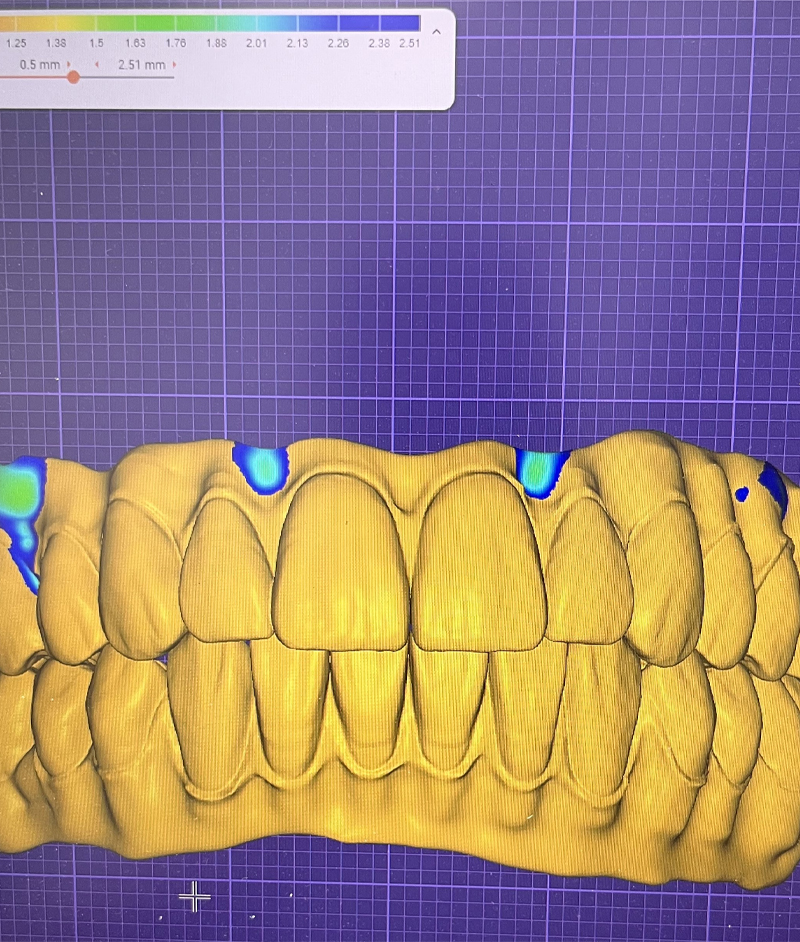

Leveraging cutting-edge design software, we merge high-resolution photographs with 3D models of your new smile, allowing you to see the transformation before treatment even begins. This digital blueprint guides the creation of 3D-printed surgical guides, ensuring each implant is placed with absolute precision according to the final intended position of your teeth. Every detail is meticulously planned to deliver a seamless, predictable, and exceptional result.

Leveraging cutting-edge design software, we merge high-resolution photographs with 3D models of your new smile, allowing you to see the transformation before treatment even begins. This digital blueprint guides the creation of 3D-printed surgical guides, ensuring each implant is placed with absolute precision according to the final intended position of your teeth. Every detail is meticulously planned to deliver a seamless, predictable, and exceptional result.